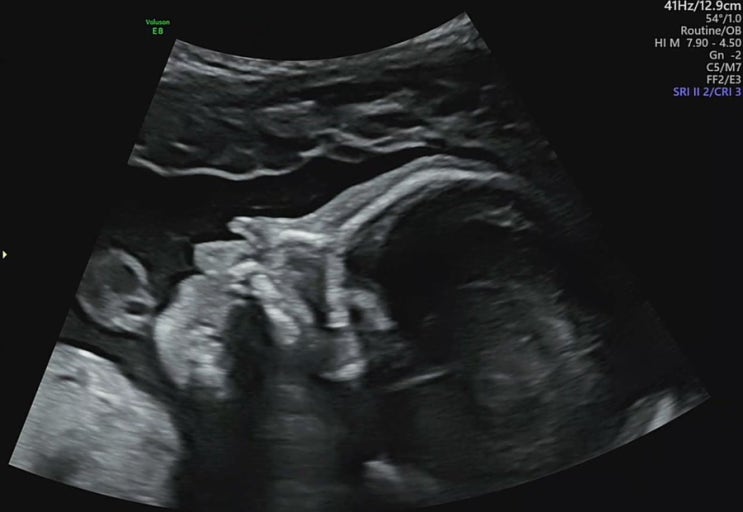

임신일기-28주, 조산기 눕눕 처방

음.. 지난주까지 잘 돌아 다니던 나.. 그런데 27주 6일 갑자기 소량의 피가 비쳤다 근데 진짜 문자 그대로 ...